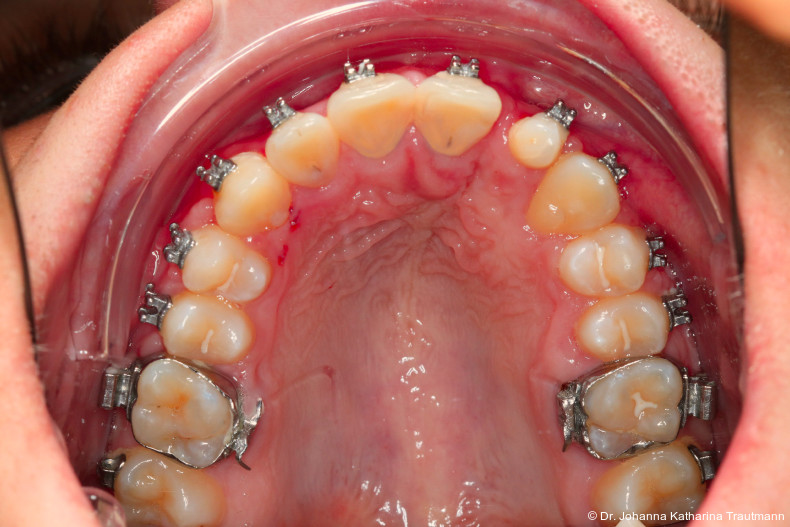

Nach transversaler Nachentwicklung der Maxilla mittels GNE nach Veltri wurde der Zahn 23 geschlossen freigelegt und an einem individualisier ten TPA nach distal angebunden. Zur Aufrichtung der Front und Mesialisierung des hypoplastischen Zahnes 22 kam zusätzlich eine 2x3Mechanik zum Einsatz. Eine rein translatorische Bewegung eines Zahnes ist auch mit einer festsitzenden Apparatur schwer zu erreichen, da der Kraftansatzpunkt nicht identisch mit dem Widerstandszentrum des Zahnes ist.7 Diese Problematik kann einerseits durch das Einbringen eines Versetzungsmomentes adressiert werden, andererseits durch eine Verlagerung des Kraftansatzpunktes. Angelehnt an den von Hong et al. beschriebenen Power Arm 8 wurde hierfür palatinal an Zahn 22 ein cranial gerichteter Hook angebracht (Abb. 3). Da Zahn 22 aufgrund seiner Hypoplasie eine verkürzte Wurzel aufwies, konnte so die Distanz zwischen Widerstandszentrum und Kraftangriffspunkt effizient reduziert werden. Eine weitere biomechanische Schwierigkeit stellte das geringe Alveolarknochenangebot im Spalt bereich mesial von 22 dar. In Bereichen mit Knochendefizit verschiebt sich das Widerstandszentrum nach apikal und wie in diesem Fall zusätzlich nach distal.9, 10 Um dem erhöhten Risiko für Kipp bewegungen entgegenzuwirken, muss hier besonders auf die Steuerung des M/F-Quotienten geachtet werden. Der vestibulär durchgebrochene Zahn 13 benötigte keine Freilegung. Um seine korrekte Einstellung zu ermöglichen, wurde die Mesialwanderung des Zahnes 16 mithilfe des TPAs korrigiert sowie eine Mittellinienkorrektur nach links mittels 2x3 Mechanik durchgeführt.

Nach etwa zwei Jahren initialer Behandlung konnte nach abgeschlossenem Wurzelwachstum aller bleibenden Zähne (mit Ausnahme der Weisheitszähne) mit der Hauptbehandlung unter Verwendung einer vollständigen Multibracketapparatur von 7 bis 7 im Ober und Unterkiefer begonnen werden. Die vergleichsweise lange Vorbehandlung erscheint zwar auf den ersten Blick behandlungszeitverlängernd, sorgt jedoch für eine deutlich bessere Mundhygienefähigkeit sowie für eine Reduktion des apparativen Aufwandes und der biomechanischen Komplexität in der Hauptbehandlungsphase. Diese Faktoren stehen in engem Zusammenhang mit Patientenkomfort und Motivation.

Im Rahmen der Multibrackettherapie wurde bewusst der Zahn 13 aus dem Hauptnivellie rungsbogen ausgelassen, um Kippungen und Asymmetrien im Zahnbogen zu vermeiden. Der Zahn 23 wurde locker mit einer Distanz ligatur angebunden, um eine weitere Bewegung nach vestibulär zu erreichen. Auf einem 0.019" x 0.025" Stahlbogen erfolgte anschlie ßend mittels Umgehungsbiegung sowie eines Overlaybogens (0.014" NiTi) die Integration des Zahnes 13 in den Zahnbogen. Die Zwischendiagnostik nach einem Jahr festsitzender Behandlung zeigte eine gelungene Bisshebung bei guter Nivellierung des Okklusionsplanums und orthoaxialer Einstellung der Frontzähne. Die Zahnbögen präsentierten sich harmonisch ausgeformt, es zeigte sich jedoch eine verbleibende Torqueproblematik an bei den Oberkiefereckzähnen. Nach Freilegung und Einstellung verlagerter Eckzähne ist eine korrekte Torque und Angulationssteuerung häufig eine Herausforderung. Während vestibulär verlagerte Zähne zu gingivalen Rezessionen neigen, behalten palatinal verlagerte Zähne oft ihre palatinale Wurzelstellung bei.13, 14 Die genutzte MBTPrescription der Brackets bietet die Möglichkeit, zwischen +7°, 0° und –7° Torque zu wählen.15 In einem 0.022" System ist bei Verwendung eines 0.019" x 0.025" Bogens jedoch mit einem Torqueverlust von etwa 10° zu rechnen.16